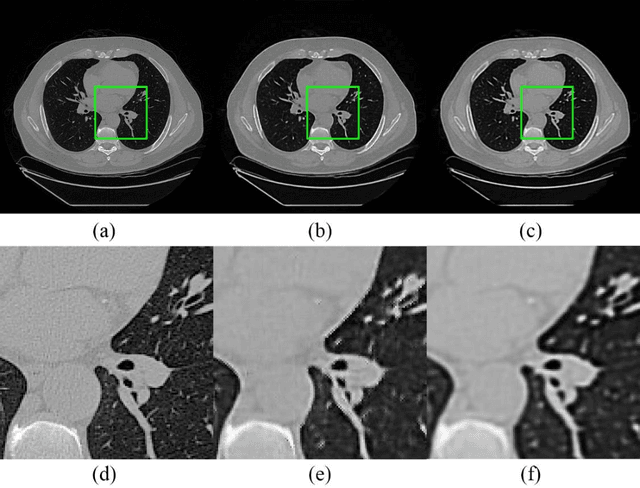

Abstract:Radiomics is an active area of research focusing on high throughput feature extraction from medical images with a wide array of applications in clinical practice, such as clinical decision support in oncology. However, noise in low dose computed tomography (CT) scans can impair the accurate extraction of radiomic features. In this article, we investigate the possibility of using deep learning generative models to improve the performance of radiomics from low dose CTs. We used two datasets of low dose CT scans -NSCLC Radiogenomics and LIDC-IDRI - as test datasets for two tasks - pre-treatment survival prediction and lung cancer diagnosis. We used encoder-decoder networks and conditional generative adversarial networks (CGANs) trained in a previous study as generative models to transform low dose CT images into full dose CT images. Radiomic features extracted from the original and improved CT scans were used to build two classifiers - a support vector machine (SVM) and a deep attention based multiple instance learning model - for survival prediction and lung cancer diagnosis respectively. Finally, we compared the performance of the models derived from the original and improved CT scans. Encoder-decoder networks and CGANs improved the area under the curve (AUC) of survival prediction from 0.52 to 0.57 (p-value<0.01). On the other hand, Encoder-decoder network and CGAN can improve the AUC of lung cancer diagnosis from 0.84 to 0.88 and 0.89 respectively (p-value<0.01). Moreover, there are no statistically significant differences in improving AUC by using encoder-decoder network and CGAN (p-value=0.34) when networks trained at 75 and 100 epochs. Generative models can improve the performance of low dose CT-based radiomics in different tasks. Hence, denoising using generative models seems to be a necessary pre-processing step for calculating radiomic features from low dose CTs.

Abstract:Radiomics is an active area of research in medical image analysis, the low reproducibility of radiomics has limited its applicability to clinical practice. This issue is especially prominent when radiomic features are calculated from noisy images, such as low dose computed tomography (CT) scans. In this article, we investigate the possibility of improving the reproducibility of radiomic features calculated on noisy CTs by using generative models for denoising.One traditional denoising method - non-local means - and two generative models - encoder-decoder networks (EDN) and conditional generative adversarial networks (CGANs) - were selected as the test models. We added noise to the sinograms of full dose CTs to mimic low dose CTs with two different levels of noise: low-noise CT and high-noise CT. Models were trained on high-noise CTs and used to denoise low-noise CTs without re-training. We also test the performance of our model in real data, using dataset of same-day repeat low dose CTs to assess the reproducibility of radiomic features in denoised images. The EDN and the CGAN improved the concordance correlation coefficients (CCC) of radiomic features for low-noise images from 0.87 to 0.92 and for high-noise images from 0.68 to 0.92 respectively. Moreover, the EDN and the CGAN improved the test-retest reliability of radiomic features (mean CCC increased from 0.89 to 0.94) based on real low dose CTs. The results show that denoising using EDN and CGANs can improve the reproducibility of radiomic features calculated on noisy CTs. Moreover, images with different noise levels can be denoised to improve the reproducibility using these models without re-training, as long as the noise intensity is equal or lower than that in high-noise CTs. To the authors' knowledge, this is the first effort to improve the reproducibility of radiomic features calculated on low dose CT scans.